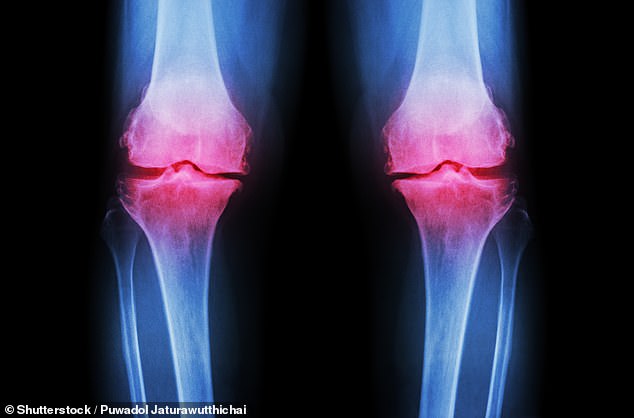

Osteoporosis, diagnosed via a Dexa scan, is characterized by a bone mineral density score below -2.5, with osteopenia falling between -1 and -2.5. The condition weakens bones over time, often remaining undetected until a fracture occurs. While treatments include medication and lifestyle adjustments, the study reinforces the role of exercise and nutrition in supporting bone health. Experts recommend regular physical activity, adequate protein intake, vitamin D supplementation, and avoiding smoking and excessive alcohol consumption as key strategies for maintaining musculoskeletal integrity in aging populations.